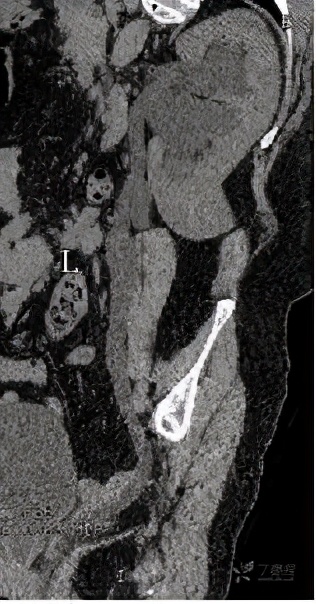

检查完成后,CT也印证了双肾积水的表现。

但是,双侧输尿管走行区未见明显梗阻的因素。

同时也发现了异常表现:双侧输尿管开口过低,似乎不是正常的膀胱三角区。

在增强CT检查的时候,得到了如下检查图像

检查图像显示,该病人的双侧输尿管于膀胱开口处过低,还伴有左侧部分双肾盂、输尿管畸形,这些图像给我们的印象是:是不是存在异位开口的可能?